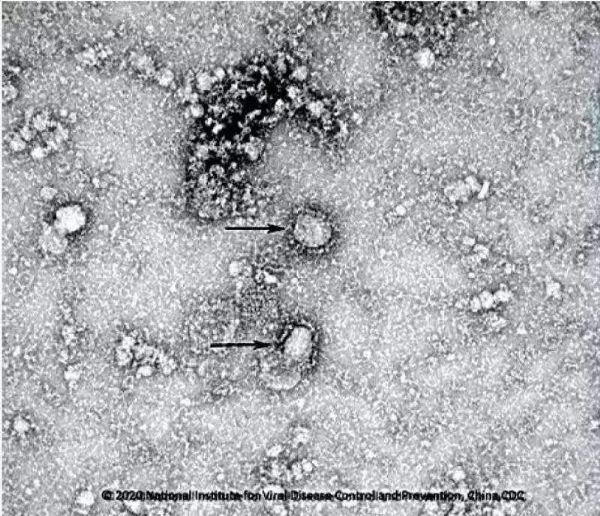

新春將近,驚聞武漢疫情疾變,新春佳節(jié)舉國上下共同打響了疫情阻擊戰(zhàn),全國人民被迫迎戰(zhàn)。國家主席習(xí)近平親自指揮調(diào)度,國家總理李克強親臨疫區(qū)一線巡視病情,疫情就是命令,一方有難八方支援,全國各地的醫(yī)護工作者,緊急馳援武漢,“我是黨員,我先上”“若有戰(zhàn),召必回”“等你回來,我娶你”一處處、一幕幕上演著... ...